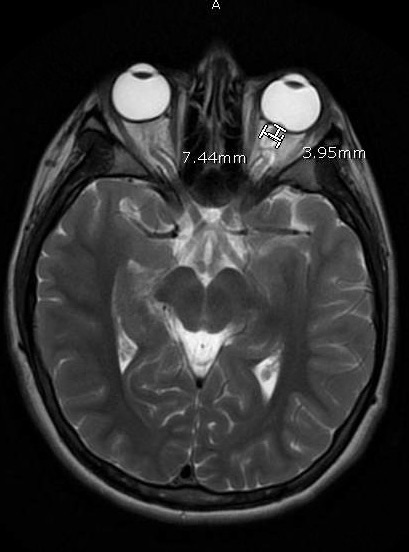

Her headaches had been occurring for 1 year at the time of her presentation, and she described them as a sharp shooting pain with occasional “vision blackouts.” Two months prior to presentation, her headaches had progressively worsened with associated photophobia, phonophobia, and emesis. She was found to have papilledema on funduscopic examination by an ophthalmologist. Findings of computed tomography scans of the head were normal. MRI of the orbits showed findings consistent with intracranial hypertension (IH) (Figure), and magnetic resonance venography (MRV) findings were concerning for superior sagittal sinus thrombosis. She denied taking any medications, specifically oral contraceptives, vitamin A, steroids, and antibiotics.

Figure. MRI of the orbits showed findings consistent with intracranial hypertension.